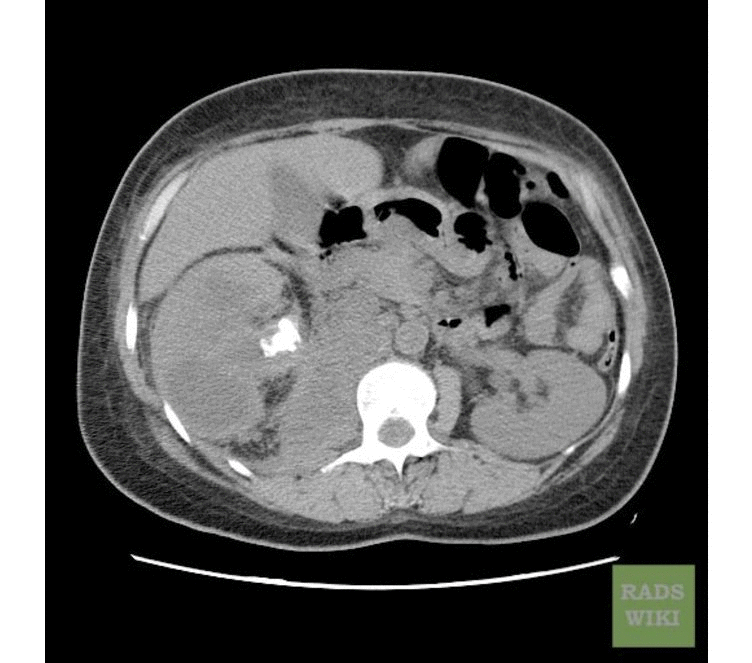

Пиелонефрит кт